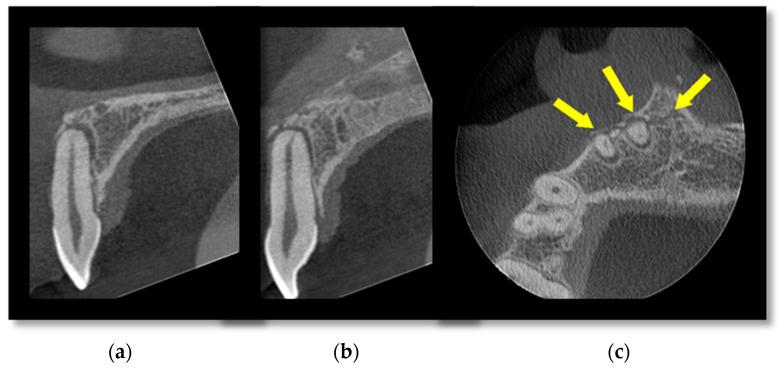

The assessment and management of facial trauma in an acute setting is one of the core services provided by oral and maxillofacial units in the United Kingdom. Imaging is a pre-requisite for appropriate diagnosis and treatment planning, with a combination of plain radiographs and medical-grade CT being the mainstay. However, the emergence of cone beam CT in recent years has led to its wider applications, including facial trauma assessment. It can offer multi-planar reformats and three-dimensional reconstruction at a much lower radiation dose and financial cost than conventional CT. The purpose of this review is to appraise its potential indications in all anatomical areas of maxillofacial trauma and provide our experience at a level 1 trauma centre.

在急性情况下对面部创伤进行评估和处理是英国口腔颌面科室提供的核心服务之一。影像学检查是进行恰当诊断和治疗规划的先决条件,主要依靠普通X光片和医用级CT的联合使用。然而,近年来锥形束CT的出现使其得到了更广泛的应用,包括面部创伤评估。与传统CT相比,它能够以更低的辐射剂量和经济成本提供多平面重建和三维重建。这篇综述的目的是评估其在颌面创伤所有解剖区域的潜在适应证,并介绍我们在一级创伤中心的经验。